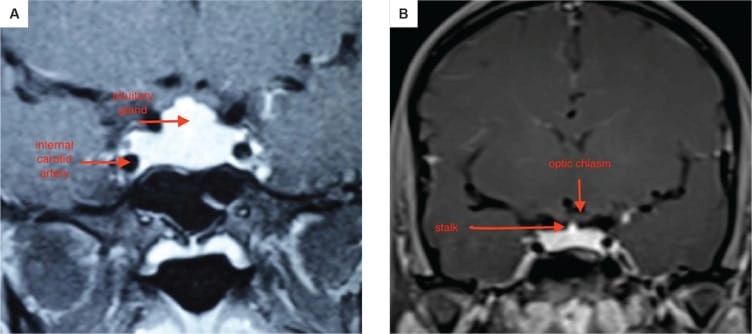

১. অবস্থান ও গঠন: পিটুইটারি গ্রন্থি একটি হাড়ের গঠন, যাকে সেলা টার্সিকা বলা হয়, তার ভিতরে বসে থাকে। এটি মাথার খুলির নিচের দিকে, স্ফেনয়েড নামক হাড়ে একটি গহ্বর, যা নাকের পেছনে অবস্থান করে। এটি অপটিক কায়াজম (optic chiasm) এর নিচে অবস্থিত, যেখানে দুটি চোখের স্নায়ু পরস্পর ক্রস করে। এটি ইন্টারনাল ক্যারোটিড আর্টারি নামক দুটি প্রধান রক্তনালীর মাঝখানে থাকে।

MRI-তে এই হাইপারপ্লাসিয়া সাধারণত গম্বুজ-আকৃতির ও সমমিত হয় এবং হোমোজেনাস সিগনাল ইন্টেনসিটি দেখায়, যেখানে সাধারণ নন-ফাংশনাল পিটুইটারি অ্যাডেনোমা নানা আকার ও অসমতা নিয়ে দেখা যায়।